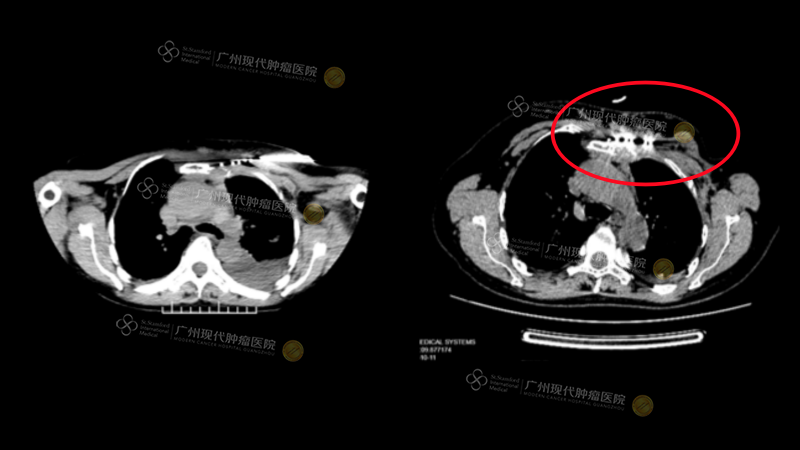

王教授通过一系列典型病例,生动诠释了微创技术的临床应用价值。其中,一例乳腺癌并骨转移患者,治疗前疼痛评分(NRS)高达10分,使用大剂量常规止痛药物仍效果不佳;经MDT讨论后为其施行了CT引导下的冷冻消融术,术后患者疼痛得到显著缓解,生活质量获得明显改善。

●●

(施行冷冻消融术)

(治疗后NRS评分)

另一例乳腺癌术后复发伴胸壁、骨转移的患者,同样面临常规药物镇痛不满意的困境(NRS 8分);在采用放射性粒子植入术后,患者疼痛得到有效控制,生活质量和活动能力(Karnofsky评分)均较前提升。

(施行粒子植入术)